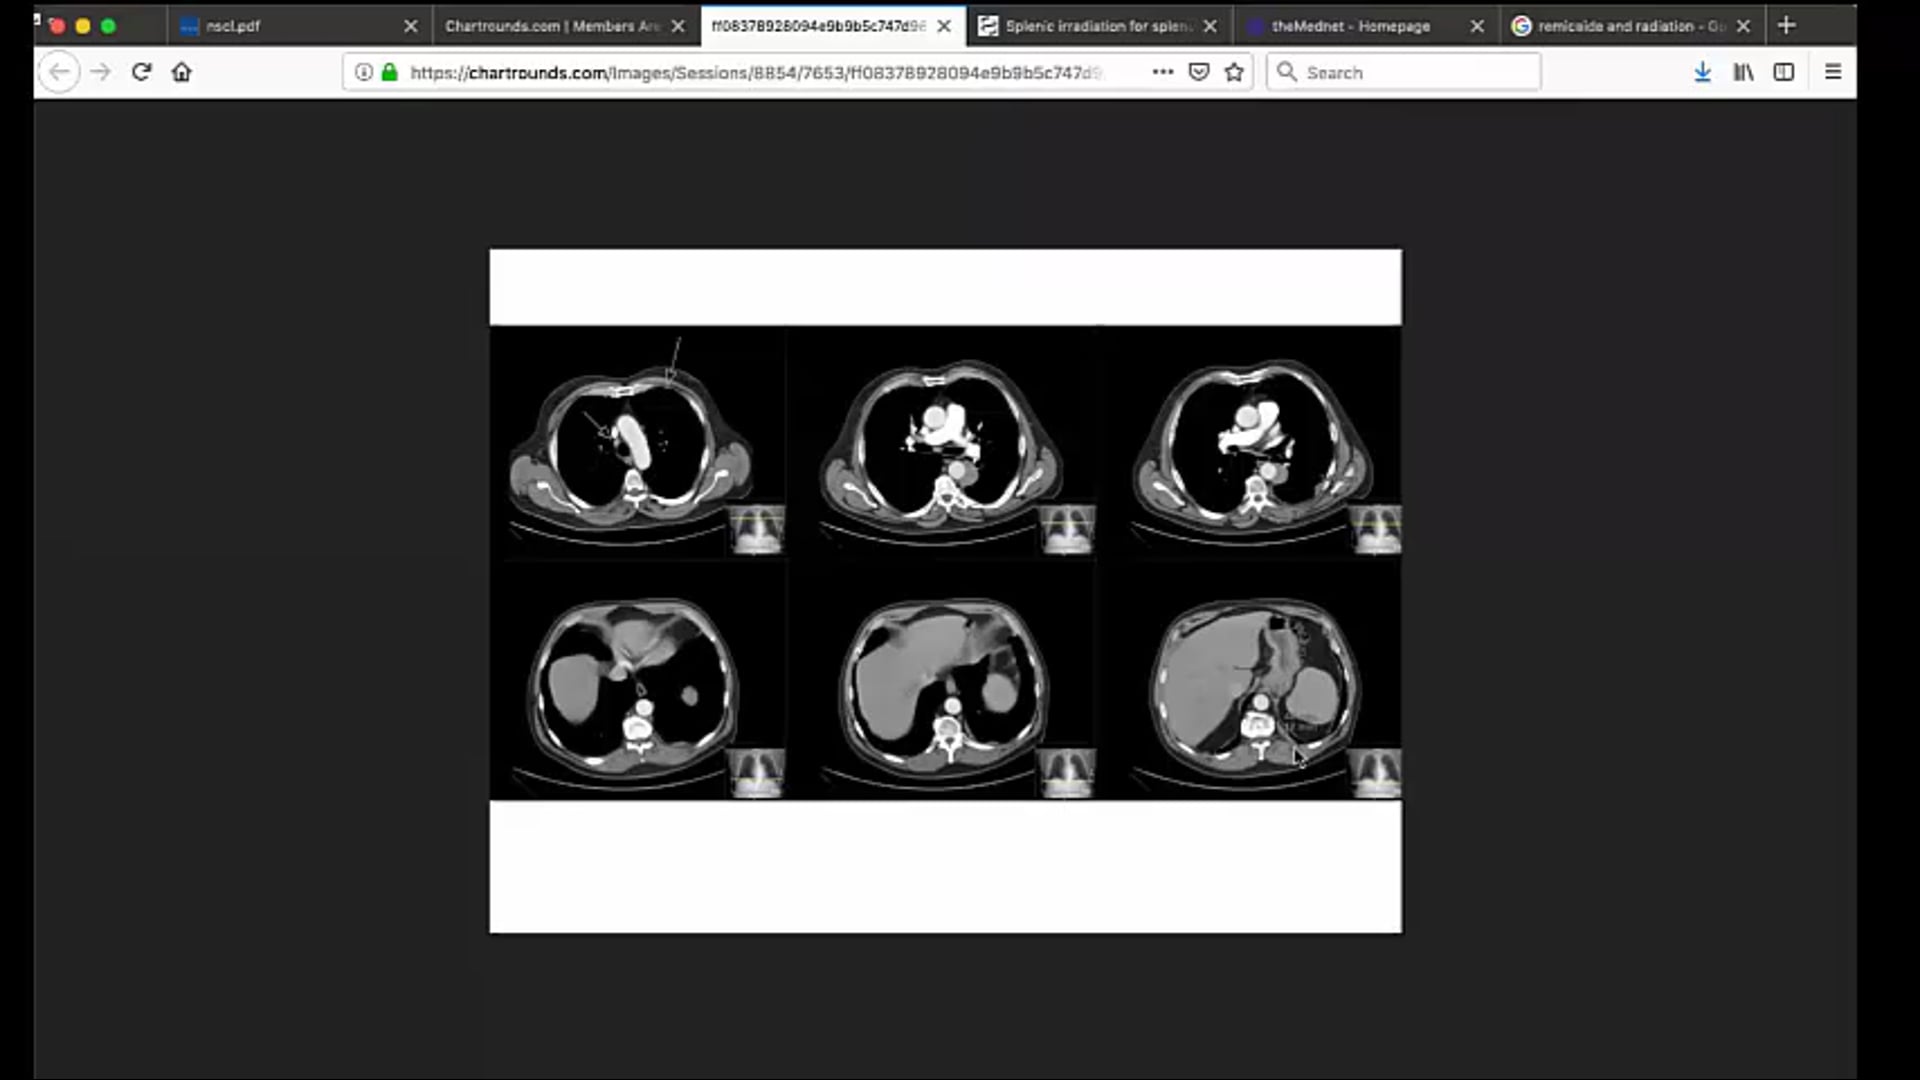

oligometastatic metastatic disease, genetic sequencing, MRI,

09/02/2021 - Dr. Candice Johnstone - Radiation Oncology - US Lung

02/10/2022 - Dr Candice Johnstone - Radiation Oncology - Lung and Palliative